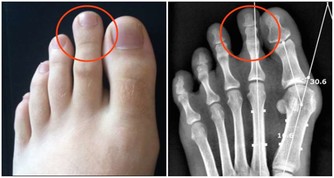

二、無法治癒的腳掌疼痛

糖尿病患者的血糖濃度升高會導致腳部神經的破壞,具體表現就是經常會發生由於壓力或不小心的摩擦而引起切傷、刮傷或刺激。如果您發現您的腳掌經常疼痛,那麼您需要仔細留意一下,您的足底皮膚是不是會紅腫、皸裂、長水皰、腳癬及腳趾變形等症狀。如果有上述的一部分症狀,您就需要去醫院檢查一下您的血糖是否已經很高了。

對於高血糖的朋友來說,每天用溫和的中性肥皂水洗腳很有必要的,而且洗腳時水溫應在35℃為宜,水溫不能過高,因為會對糖尿病患者造成腳部傷害。同時,浸泡腳的時間不能太長,只要20-30分鐘就可以了。洗腳之後要用純棉毛巾輕輕擦腳,以免造成腳部損傷。